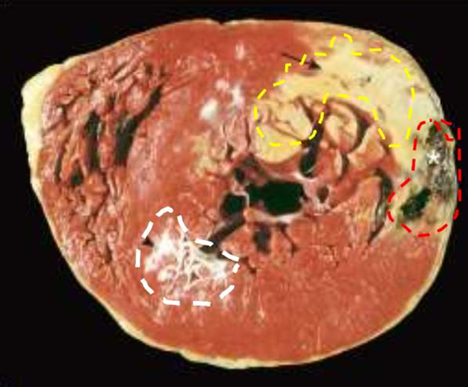

IHD: Myocardial infarction

Acute Myocardial Infarction

Yellow area = necrosis

arrow head = anterior scar (remote infarction)

star = myocardial haemorrhage due to ventricular rupture (was the acute cause of death

Reperfused myocardial infarction

Reperfused myocardial infarction. The transverse heart slice exhibits a large anterior wall myocardial infarction that is hemorrhagic because of bleeding from damaged vessels. The posterior wall is at the top.